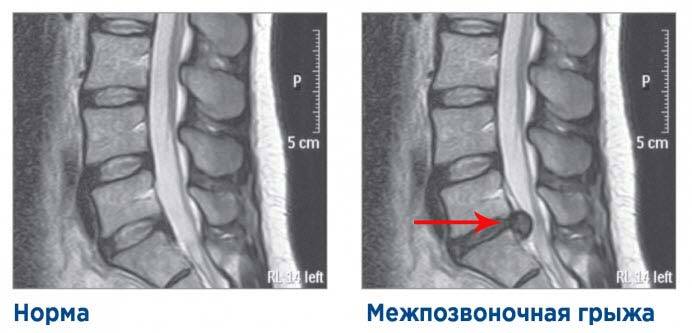

При грыже поясничного / шейного / грудного отдела позвоночника

Тут немножко нужно разобраться, что вообще такое грыжи. Выход органа из занимаемой им полости называется грыжей. Межпозвоночная грыжа — это разрыв межпозвоночного диска (сдвиг ядра с соединительными веществами и прорыв фиброзного кольца). Грыжа является самым часто встречающимся проявлением остеохондроза поясничного отдела или быть последствием травмы.